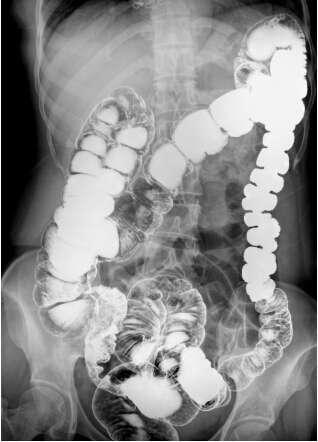

目前主流的DR成像面積都是17英寸×17英寸方形成像,這在臨床應用中有巨大的優勢。動態DR在常規DR的基礎上實現新的技術突破,尤其是在成像尺寸上也是有了新的突破,也能實現17英寸×17英寸方形動態影像的輸出。可以說這是一個革命性的突破。比如:以前做一個全消化道造影,需要調整球管跟隨著造影劑的流向進行實時觀察,往往只能觀察到局部的情況。一個正常體型的成年人做一個全消化道造影至少需要點三到四張片子才能看全,并且非常麻煩。

現在的動態DR,成像視野非常大,一改過去圓形成像傳統,的確大大有益于臨床醫生的便捷操作。一個幅面就能夠把一個正常的成年人的全消化道看全,并且影像非常的清晰,可以大幅減少觀察時間,減少病人吃線量。